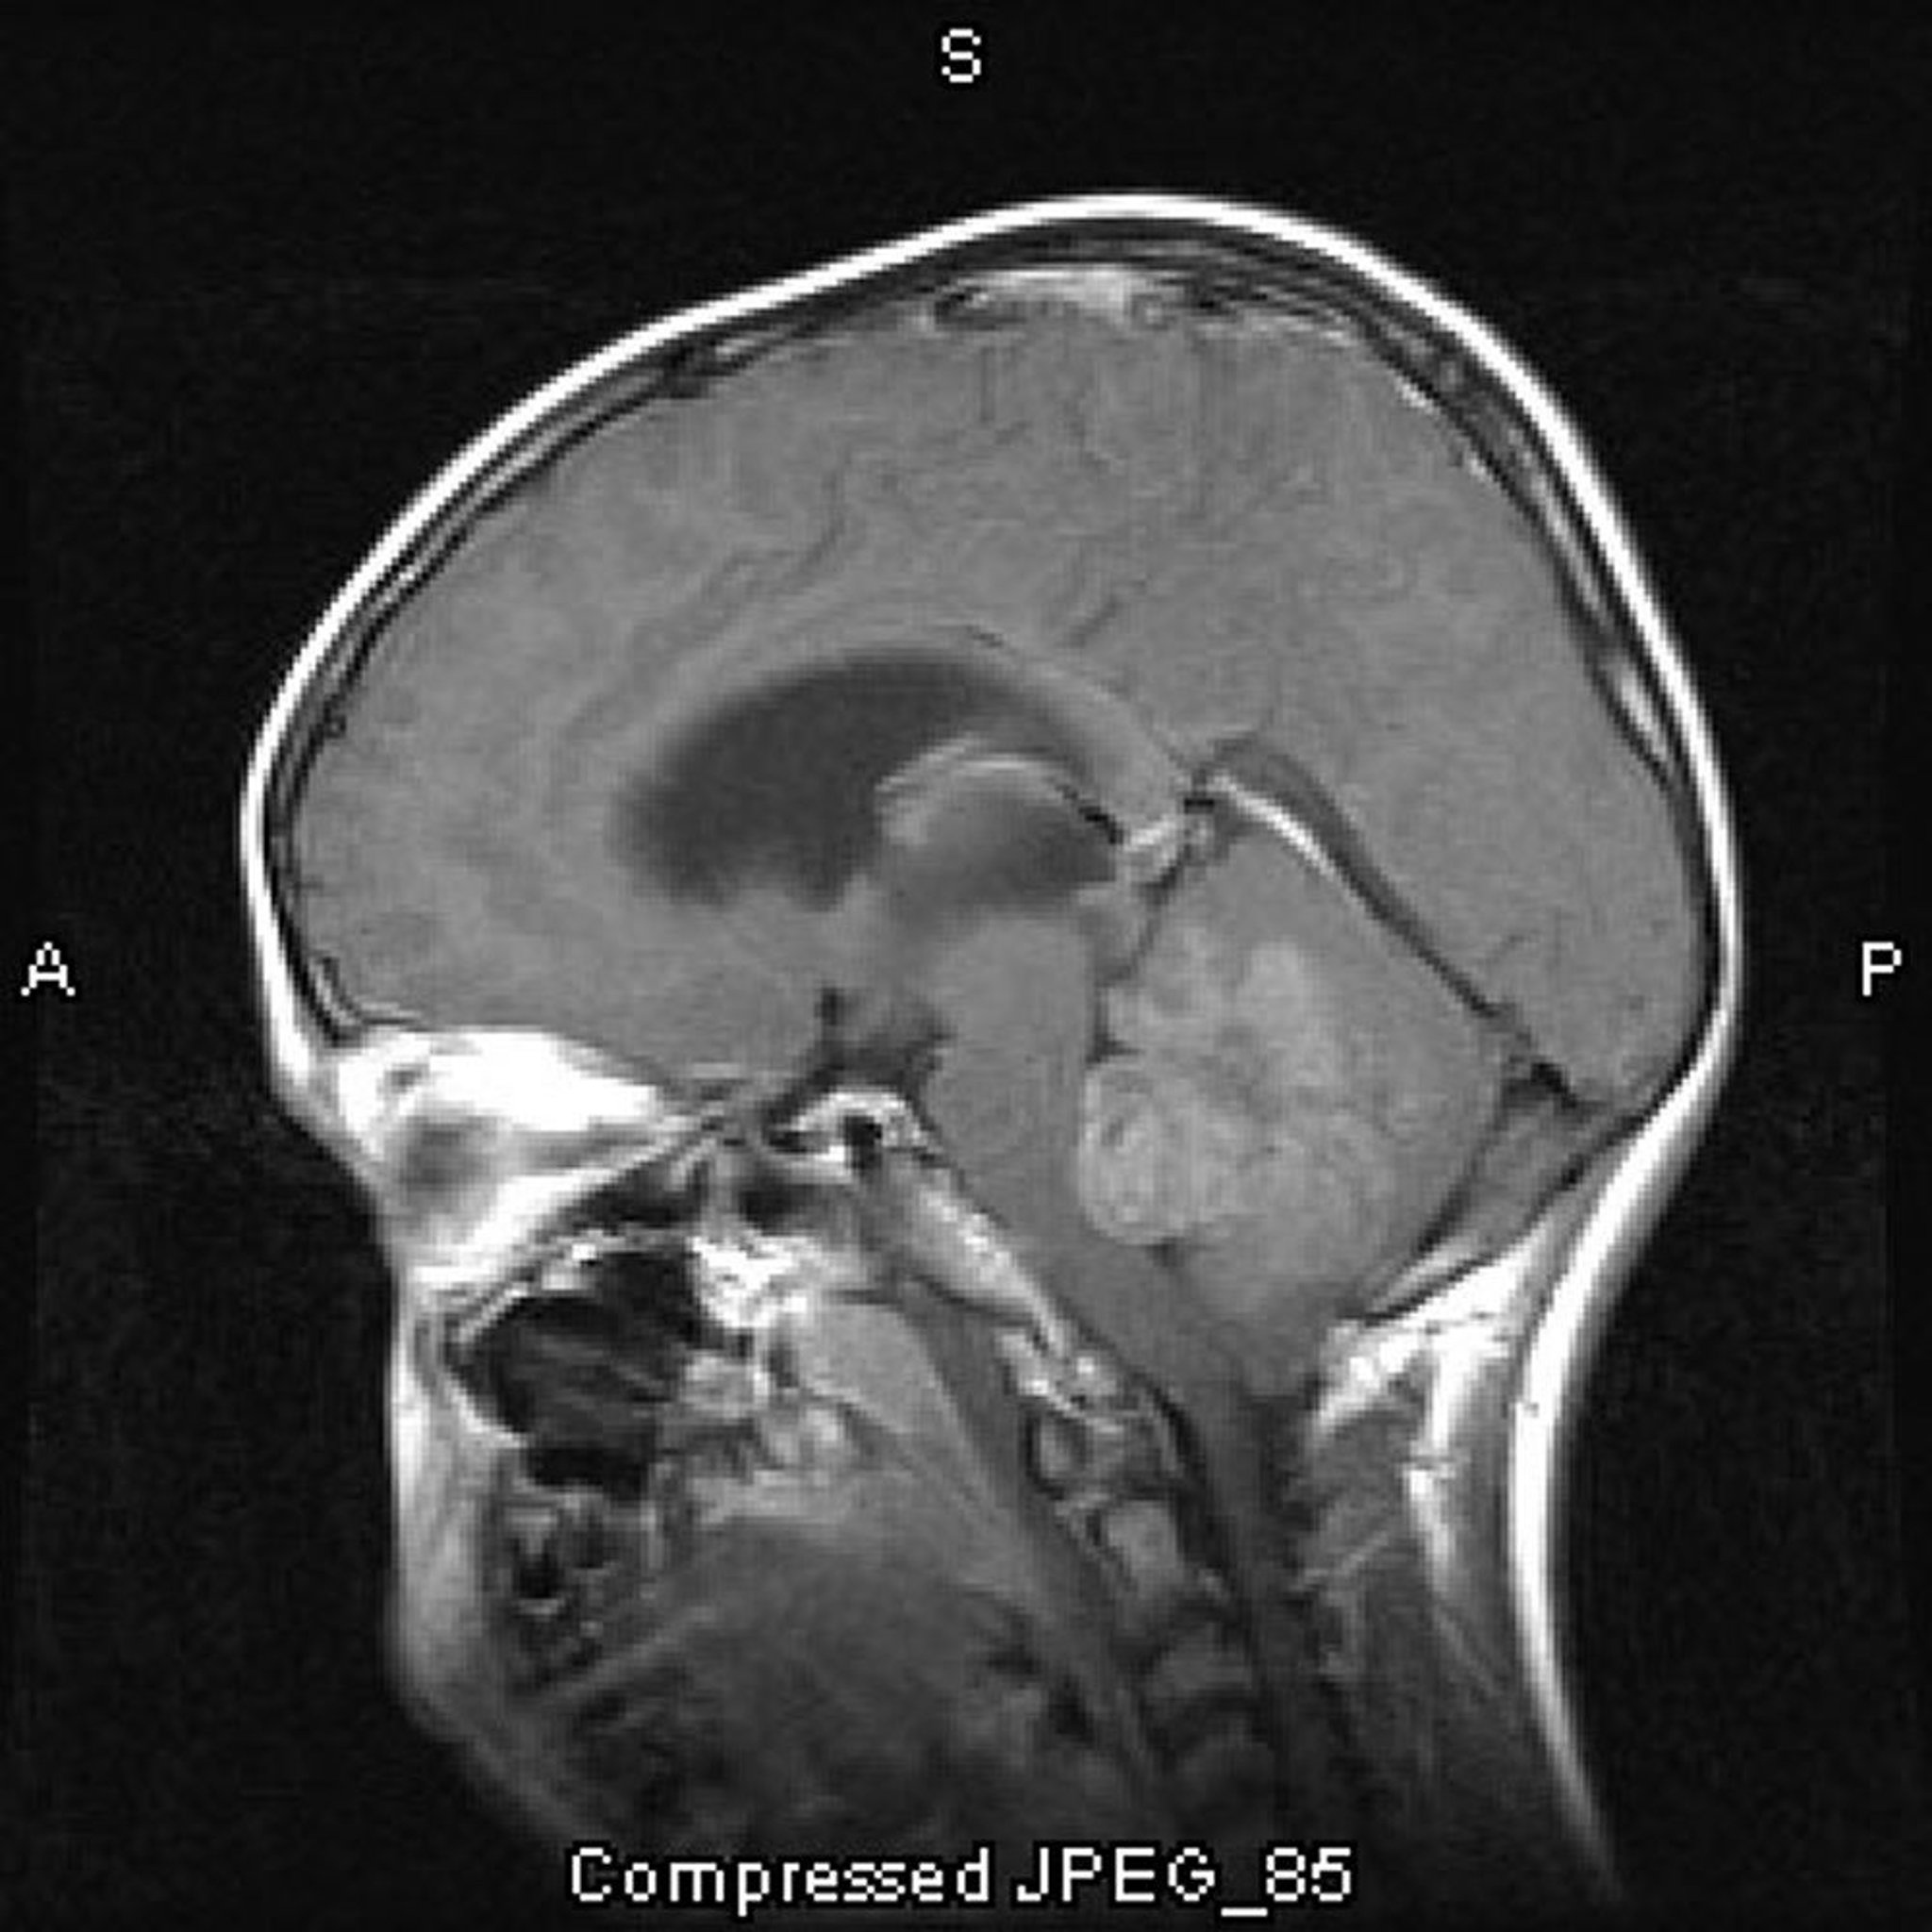

Медуллобластома

На этом снимке МРТ с контрастированием показана медуллобластома, которая развивается в крыше 4-й желудочка и обтурирует его

Image courtesy of William R. Shapiro, MD.